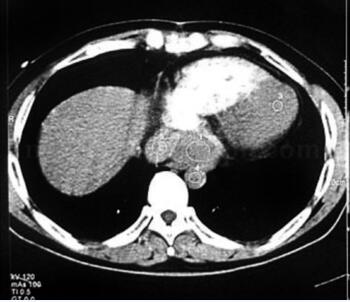

腹部CT未见异常;UCG提示左室肥厚,舒张功能降低;MIBG(-);奥曲肽显像示双侧颈动脉及纵隔右前方异常放射性浓聚区,考虑多发异位嗜铬细胞瘤;心脏增强CT显示心脏后方肿瘤(图31-4);颈部增强CT见左、右侧颈动脉分叉处直径5cm、3cm肿瘤(图31-5);冠脉造影回旋支近段发出心房支向瘤体供血,造影中有两次血压突然增高,最高达200/125mmHg,经硝普钠等治疗后可控制正常。

图31-4 心脏增强CT示心脏后方肿瘤

MRI和CT对明确和证实心脏嗜铬细胞瘤并了解其形状特点、周围浸润方面有重要价值,CT要求为高速增强CT,而慢速CT不能适应心脏处于快速运动中的特点,亦难以捕捉肿瘤与心脏腔室增强剂摄取差异的短暂时刻。与CT相比,MRI对软组织有更高的分辨率和敏感性,嗜铬细胞瘤MRI在T2像中呈高信号,而心脏血流在T2像中呈低信号,因而MRI诊断心脏嗜铬细胞瘤较CT扫描更具优势。超声心动图对发现心脏嗜铬细胞瘤意义值得研究,文献报道普通超声心动图和经食道超声心动图对心脏嗜铬细胞瘤均有很高的检出率(4/5和7/7),并总结出其特征为“位于房室间沟邻近心外膜冠状动脉的卵圆形、颗粒状肿瘤”,将经食道超声列为最有效的检出手段之一。冠脉造影有利于明确肿瘤血供情况,指导手术设计及术前准备,但操作风险大,宜作充分准备。